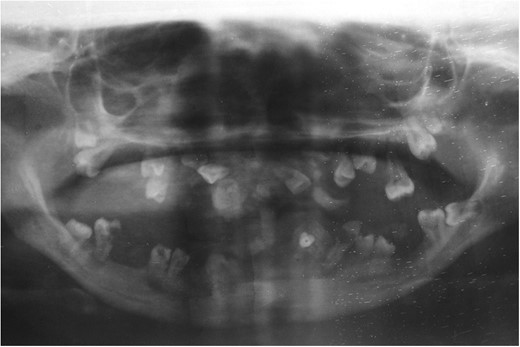

Her younger sister with age 17 years also presented 4 months later with similar complaints (Fig. 4). She also had normal deciduous teeth but did not have any permanent teeth eruption. She had difficulty in mastication and speech as well. She was mentally sound and did not have any other abnormalities. All her routine investigations were normal. X-ray (Fig. 5) and CT (Fig. 6) scan showed permanent teeth in both upper and lower arch which were malpositioned, unerupted and impacted in fibrous growth. Biopsy was taken from the gingival growth of younger sister which showed stratified squamous lining and subepithelial tissue showed collagenous fibrous connective tissue with mild chronic inflammatory cells (Fig. 7). Diagnosis of FGF was given. She underwent two stage gingivectomy 2 weeks after the initial diagnosis of FGF (Fig. 8). She is doing well and able to close her lips on post-operative follow-up (Fig. 9A). Later, prosthetic rehabilitation was done with upper and lower complete removable denture to the younger sister (Fig. 9B).

X-ray picture of younger sister showing impacted and malpositioned permanent teeth in upper and lower arch.